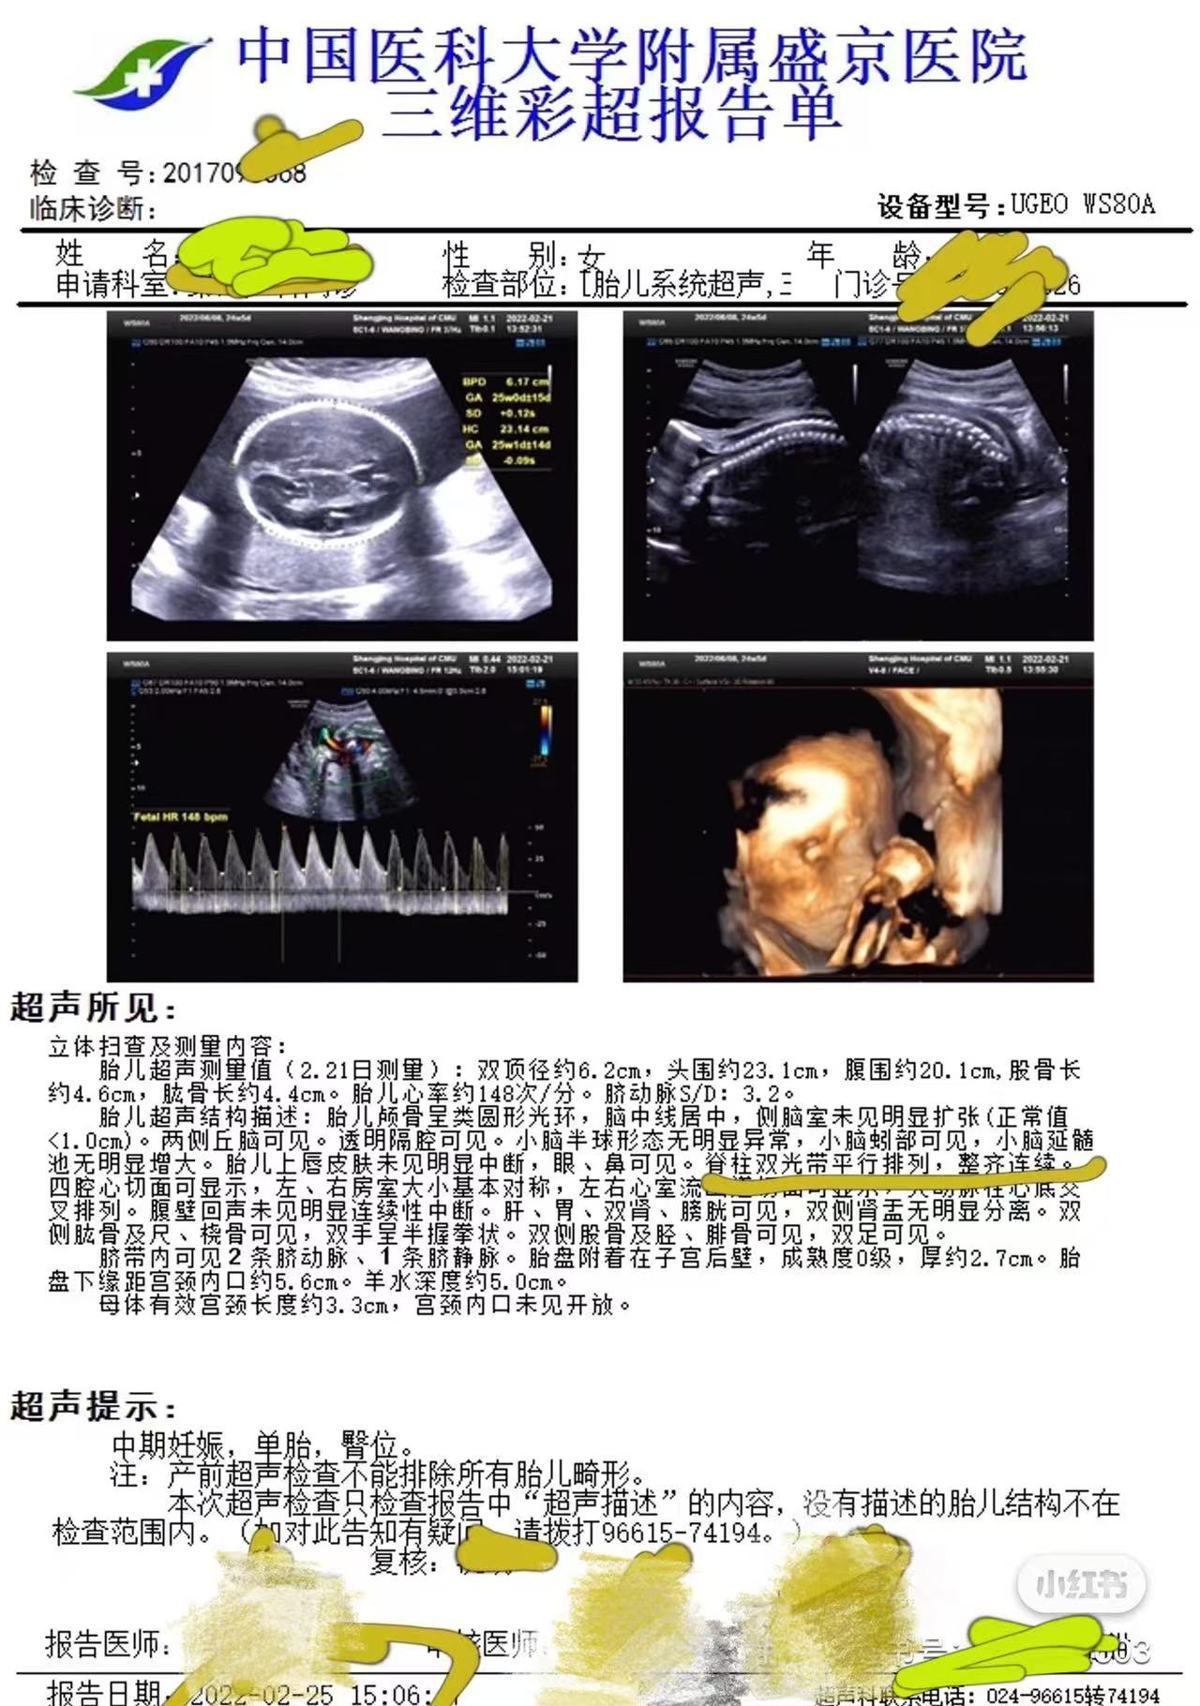

3月11日,高女士告诉极目新闻记者,2021年10月,她到盛京医院做了第一次产检并预约了后续的检查,2022年2月25日,她在盛京医院做了包括胎儿系统超声在内的大排畸检查,检查结果显示胎儿“脊柱双光带平行排列,整齐连续”,2022年6月15日,女儿出生。同年12月,女儿在核磁检查时被确诊脂肪脊髓脊膜膨出和椎管内脂肪瘤,即“脊柱裂”,“脊柱裂意味着女儿后期需要多次手术治疗,否则会足踝畸形、大小便失禁,严重的话甚至会导致下半身瘫痪。”

产前彩超显示胎儿脊柱正常(受访者供图)

高女士表示,沈阳市卫健委的调查结果仅回应了她的部分诉求,她自始至终还是没有看到盛京医院提供的彩超原始图像,“大排畸的彩超会产生多张切面图像,但医院只提供了三维彩超报告单,原始图像却没有。”2025年4月,她再次向沈阳市卫健委申诉,要求调查处理盛京医院,并请其敦促院方提供彩超原始图像,沈阳市卫健委回复称让盛京医院自行处理,但盛京医院明确表示了拒绝。据2025年6月24日盛京医院的回复内容显示,现行法律法规并未强制规定医疗机构必须向患者提供此类病案范畴内的电子影像数据复制服务。医院拒绝向患者提供孕期彩超切面影像数据的复制服务,这一做法并非出于欺瞒患者的目的,而是基于以下考虑:一方面,是为了避免患者对专业性较强的影像数据产生理解误区,从而引发不必要的担忧和误解;另一方面,也是为了促进医学事业的发展,以及保护患者和医师双方的权益。